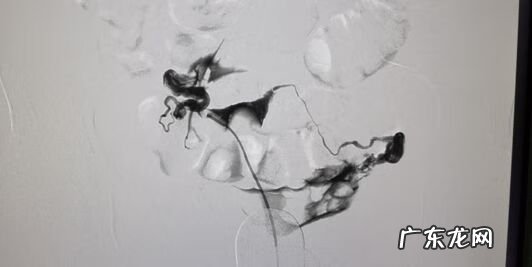

患者 , 32岁 , 顺产女婴2年后 , 未避孕未孕1年 , 外院造影提示右侧输卵管堵塞 , 介入再通治疗后 , 顺产1女 。

文章插图